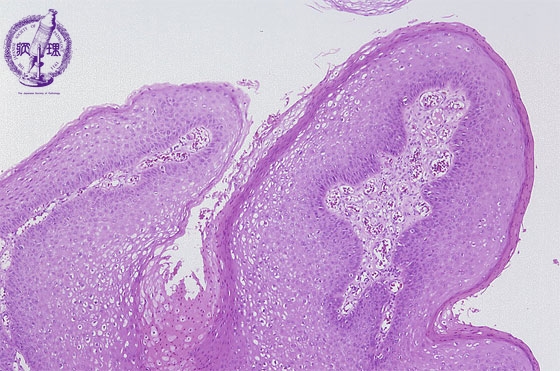

- 15.Female genital organs

- (1)Condyloma acuminatum of the vulva

Histology (HE stain, low power): Papillary proliferation of squamous epithelium. At intraepithelial surface portion, koilocytosis with clear cytoplasm is detected (surface side of the yellow dotted line).

Click the image to see the enlarged image.